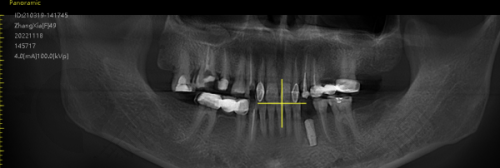

开展的种牙项目丰富,单颗、多颗、半/全口种植牙都能做。单颗种植牙价格4000元起,其中,国产种植牙4000元起,韩系种植牙5000元起,瑞士iti种植牙12500元起,德国贝格种植牙10000元起,美国皓圣种植牙4500元起,瑞典种植牙12000元起。半/全口种植牙价格方面,半/全口韩系种植牙4 - 12万元左右,半/全口瑞士种植牙7 - 25万元左右,半/全口立得用种植牙5 - 20万元左右,半/全口Allon4种植牙4 - 25万元左右。立得用种植牙技术特别有优势,上下颌各仅需4 - 6颗就能修复全口牙,省时省力还省钱。

种牙项目上,单颗种植牙价格在4680 - 20000元左右,不同品牌价格不同,比如登腾4680起、奥齿泰5600起、ITI12000起、诺贝尔12800起、ICX8900起。半/全口种植牙价格在5万 - 25万元左右,一般上下颌各采用4/6颗植体就能修复半/全口咀嚼功能。